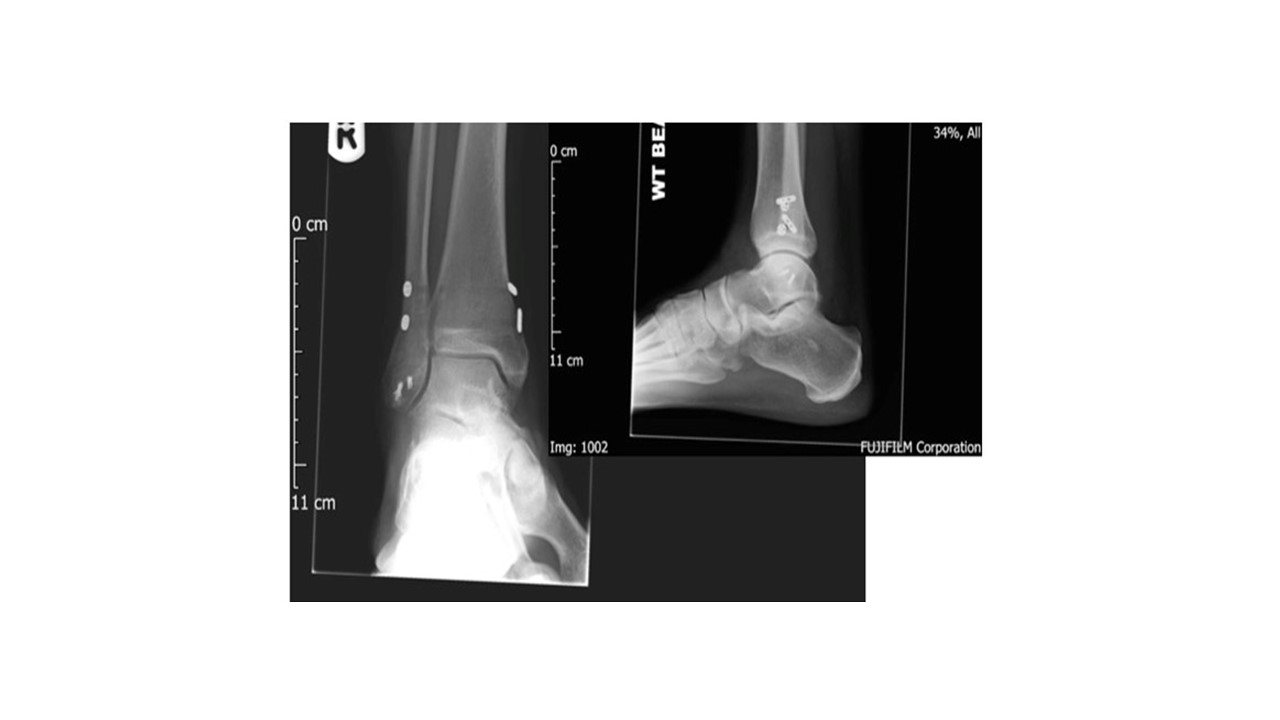

The method of surgical treatment depends on injury chronicity. Unstable, yet well-aligned syndemoses presenting within 3 months of injury require little more than arthroscopic “freshening” of the of the internal syndesmotic ligaments to create adhesion and stabilization with flexible suture-buttons or tightropes (shown below).